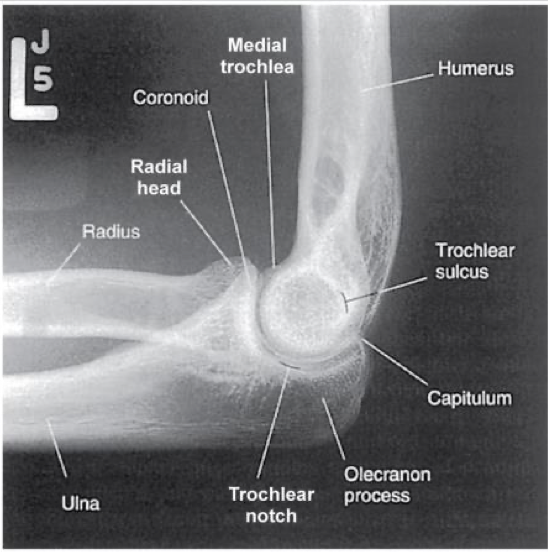

Lateral Elbow -Lateromedial Projection

Patient Position

▪ Sitting alongside or end of table

▪ Humerus abducted

▪ Entire upper limb must be at same height

Part Position

▪ Elbow flexed 90

▪ If elbow is not flexed 90, the posterior fat pad is visible**

▪ Wrist in a lateral; thumb up

▪ May need to elevate wrist slightly to keep elbow lateral

CR

▪ To elbow joint (4cm medial to olecranon process)

Collimation

▪ Same as AP

▪ MUST include soft tissues of entire elbow

Evaluation Criteria

• Three concentric arcs visible on distal humerus

Trochlear sulcus ( small, central arc)

Capitulum ( mid-sized arc)

Medial trochlea ( largest arc, outermost)

• Olecranon process in profile

• Humeral epicondyles superimposed

• Radial head partially superimposed over coronoid

• Radial tuberosity is superimposed over medial radial shaft

• Appropriate exposure factors

• Fat pads must be visible

• Elbow flexed 90

what are the 3 concentric arcs seen in a lateral elbow

trochlear sulcus (innermost), Capitulum, and trochlea (outermost)